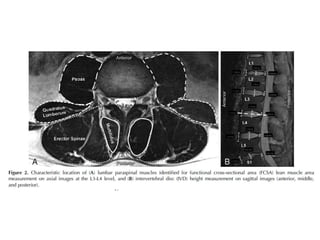

Load with respect to posture of spine